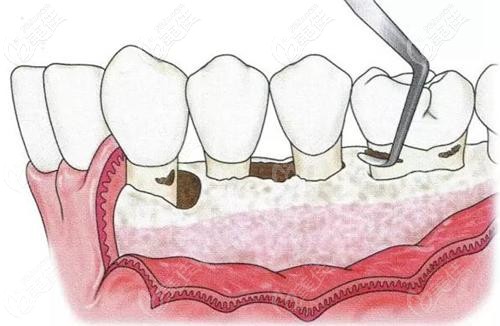

輕度牙周炎想保持40年不掉牙需要經歷這四個階段 b4531 G0 V0

牙周病可以說是“慢性殺手”,不僅會傷害牙齦,也會讓你掉牙,還會影響身體健康。那如果只是輕微的牙周炎,怎么做可以保持不掉牙呢?